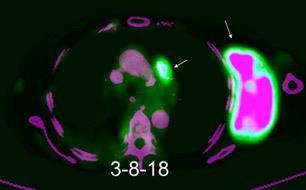

Linfoma NH de cél. B. Invasión Transtorácica.

Afectación axilar